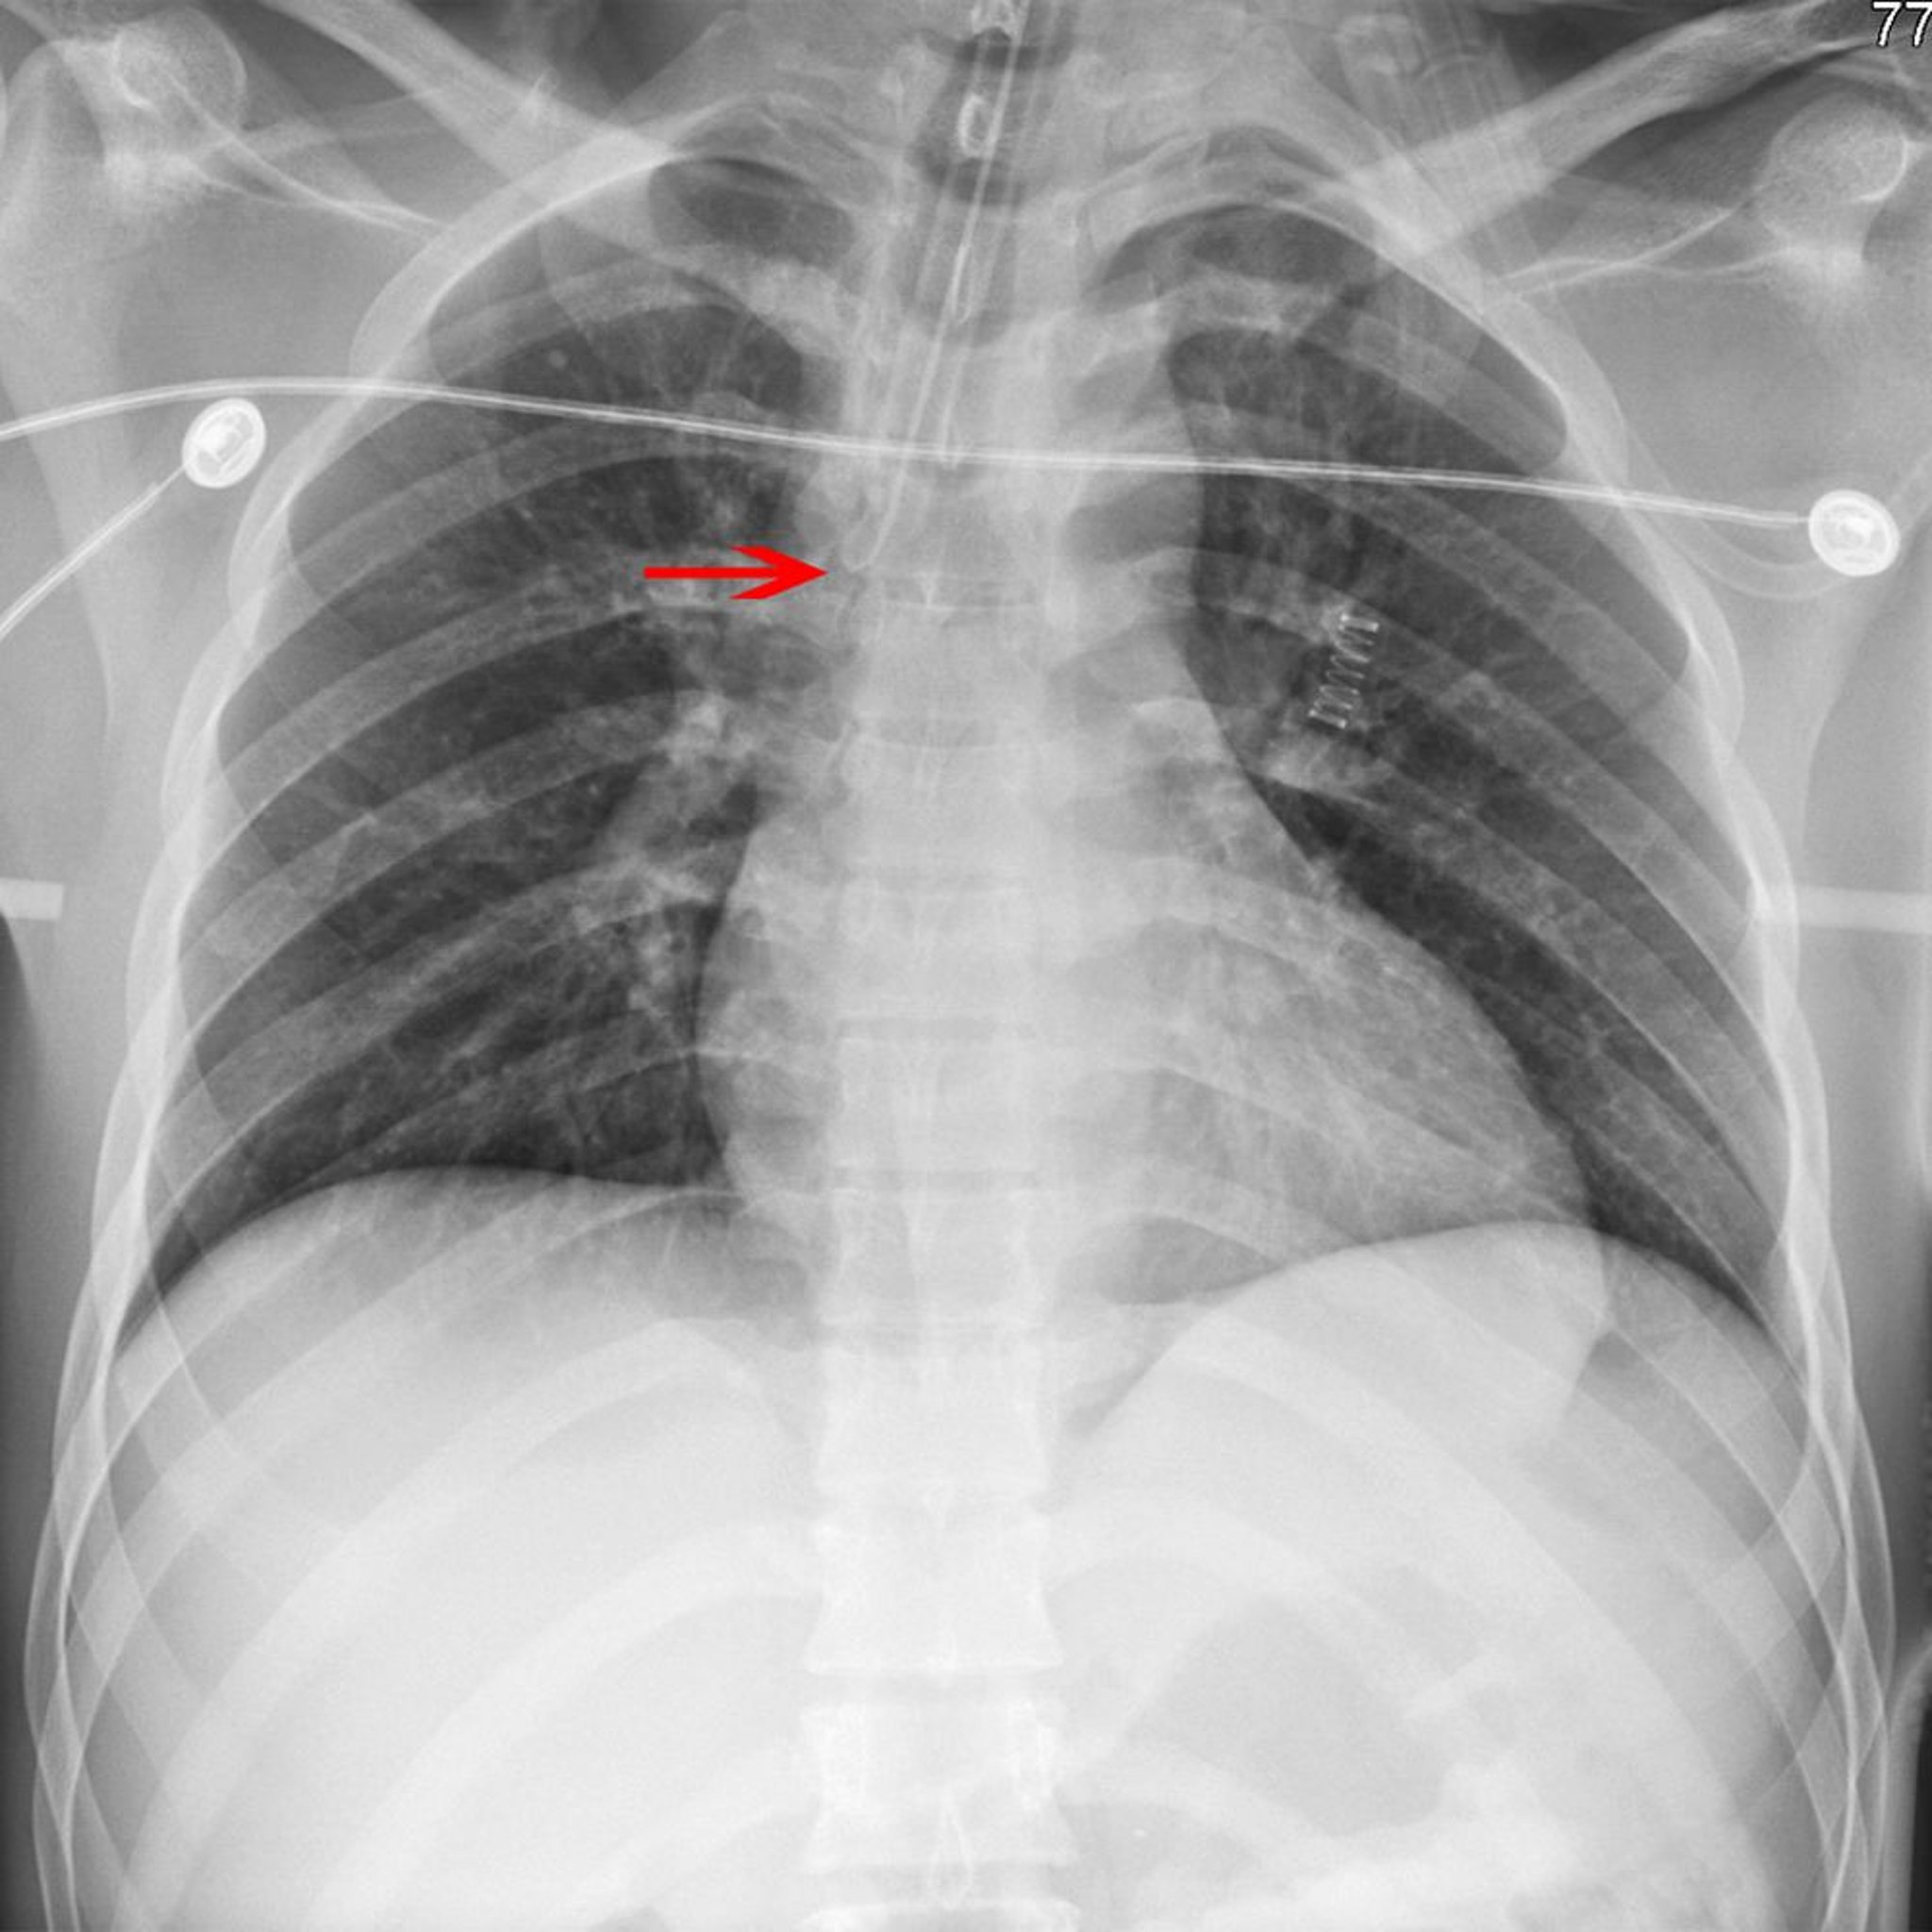

Radiografía de un tubo endotraqueal desplazado

La flecha señala la punta de un tubo endotraqueal colocado incorrectamente en el bronquio principal derecho.